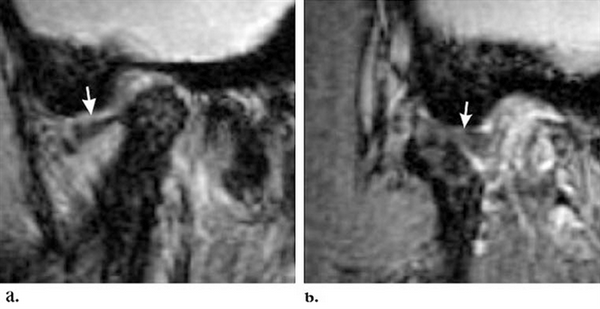

Магнитно-резонансная томография ВНЧС - невправляемый вывих. Стрелкой указано хрящевое образование, которое остается смещенным при закрытом (a) и открытом (b) рте.

На МРТ ВНЧС “застрявший диск” (a - открытый рот, b - закрытый). Стрелкой обозначена задняя поверхность хрящевого образования, которая вне зависимости от движений остается в нижнечелюстной ямке.

На МРТ вправляемый вывих. Стрелкой указано внутрисуставное образование, которое смещено кпереди при сомкнутых челюстях (a) и возвращается на место в открытом положении (b).